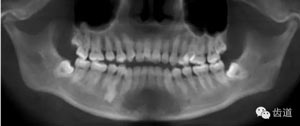

第三磨牙存,18與28牙冠小,38、48前傾阻生

中線不齊。未見(jiàn)明顯牙槽骨吸收。

下頜后縮為主要特征的骨性II類,高角,前牙開(kāi)合,上前牙略唇傾,雙側(cè)下頜升支及髁狀突不對(duì)稱,右側(cè)較左側(cè)粗壯,左側(cè)髁狀突外斜面曾有吸收,但現(xiàn)骨白線與皮質(zhì)骨已比較連續(xù),上呼吸道正常。上

頜第三磨牙牙冠較小。

牙與牙弓:25腭側(cè)完全錯(cuò)位導(dǎo)致26前移,上牙列重度擁擠,下牙列中度擁擠,上牙弓尖圓形,下牙弓卵圓形,第三磨牙牙胚存,18與28牙冠較小且形態(tài)不良